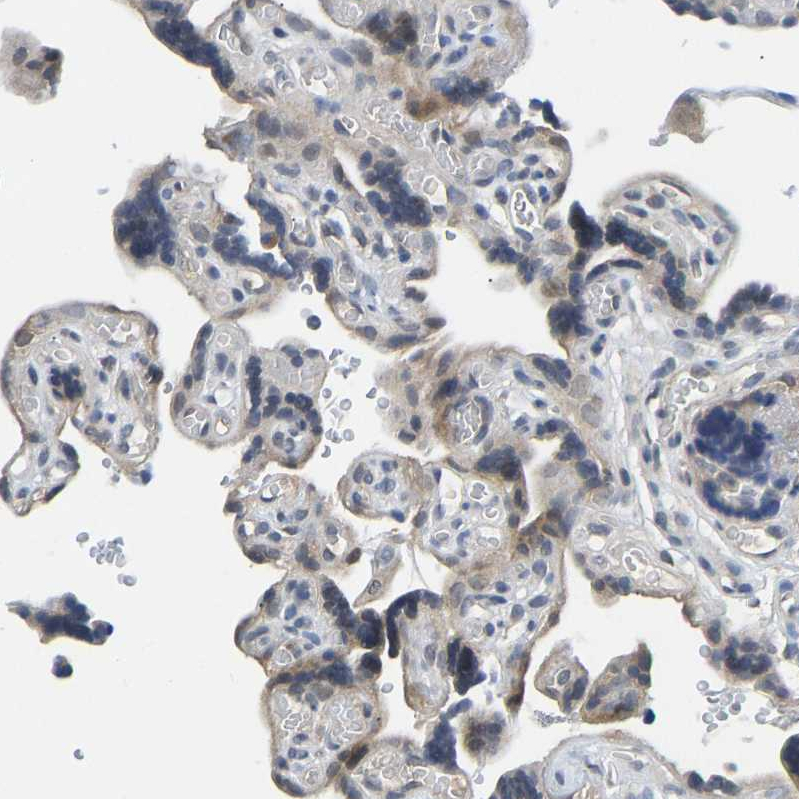

Immunohistochemistry analysis in human testis and placenta tissues using HPA017851 antibody. Corresponding NDRG3 RNA-seq data are presented for the same tissues.